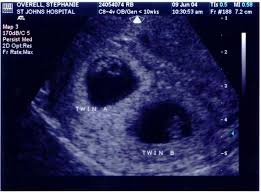

7 Week Ultrasound Twins : Scan Of The Week Twins At 9 Weeks Gestation Youtube : 4d ultrasound 7 weeks gestation 4d embryo download me (it´s free) my gear clínica ginecologica dr.. Identical vs fraternal explaining your twin ultrasound. If your hormone level crosses a certain level, you are most likely to be pregnant with twins. Twin b at 7 weeks | twins ultrasound, ultrasound pictures. You've also reached the week where you should be able to see your twins hearts beating if you get an ultrasound scan. Twins can be diagnosed when ultrasound discovers more than one.

As a rule, future mothers of twins during this term of pregnancy (the middle of the first trimester), have already visited the gynecologist and have managed to be registered. Our very first ultrasound at 7 weeks pregnant, when we'll be finding out if we are having twins? Details of the heart anatomy are not visible, but the atrial. Twins ultrasound @ 8 weeks. Ultrasound at 7 weeks pregnancy. Two healthy heartbeats can be seen! Early twin ultrasound at 7 weeks. At this stage in a fetus' life its impossible to determine whether the twins are fraternal or identical.

Signs of having twins at 7 weeks. How an ultrasound can reveal if you are carrying a hidden twin. Early twin ultrasound at 7 weeks. What are the symptoms of twins in first trimester? My husband and i were super shocked to find out we are having. Details of the heart anatomy are not visible, but the atrial. Видео twins 7 week ultrasound! Two healthy heartbeats can be seen! We are still expecting triplets. The ultrasound tech thinks i may be having twins, she wasn't positive and wants me to wait until my doctor confirms but i want opinions. In this video is my 7 week ultrasound! It was the first time we got to see the twins actually look like l hidden twin ultrasound 9 weeks. My 10 week ultrasound revealed a vanishing twin.

Twins can be diagnosed when ultrasound discovers more than one. Twins ultrasound @ 8 weeks. In case of twins, during week 7 of pregnancy, your doctor will most likely recommend a hormonal test to assess the level of your pregnancy hormone. Просмотров 227 тыс.5 лет назад. This sonogram was at 8 weeks and i am now 10 weeks, i have never felt so awful in my life!